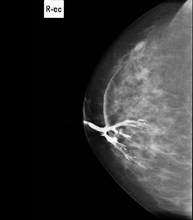

Mamografia digitalitzada

La mamografia digitalitzada és una tècnica innovadora que permet estudiar la mama amb un dosi baixa de radiació, que és més reduïda que la mamografia convencional. La imatge es digitalitza a partir d'uns bastidors especials, anomenats CR. Gràcies a aquestes tècniques de digitalització s'obtenen imatges excel·lents, sobretot en mames de difícil estudi com les glàndules que es presenten en la mamografia com una mama densa, i permet detectar millor en aquest grup de pacients les tumoracions.